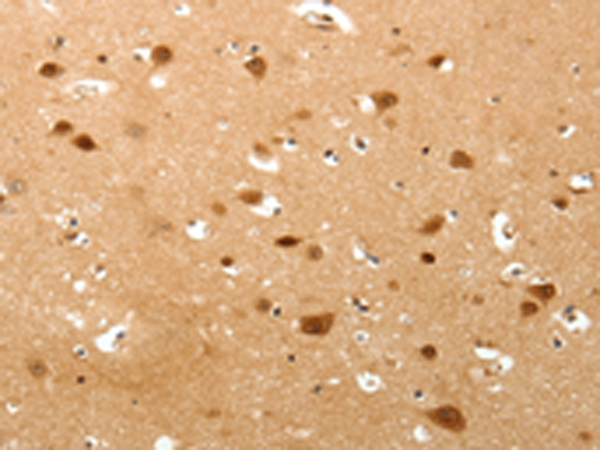

IHC positive control:

Human brain and Human lung cancer

IHC Recommend dilution:

50-200